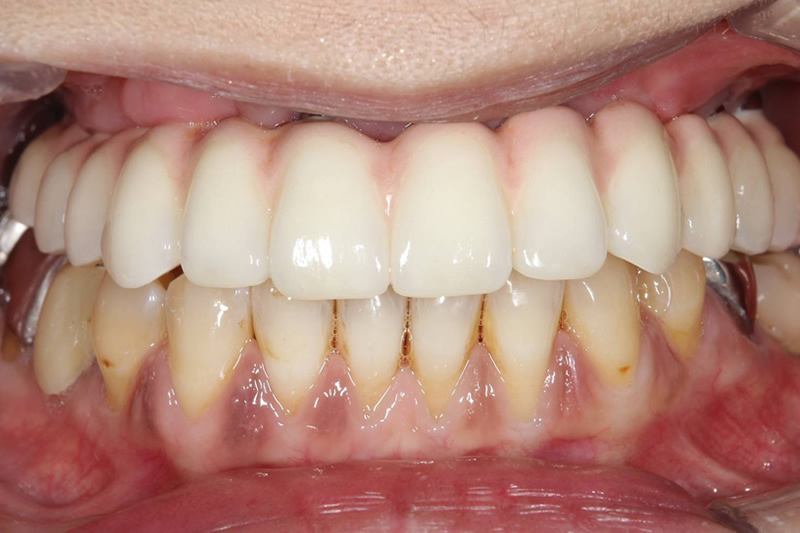

口腔内写真の比較

-

治療前

治療後

レントゲン写真の比較

| 主訴 | 被せものがとれたり、抜けたりした所を直したい。 |

|---|---|

| 治療期間 | 1年8か月 |

| 治療費 | 上顎3,465,000円(税込)・ 下顎1,430,000円(税込) |

| 治療内容 | 上顎 インプラントフィクスチャー6本・ 上部構造11歯・サイナスリフト 下顎 インプラントフィクスチャー3本・ 上部構造4歯 |

| 治療のリスク | ・インプラント手術後は反応性の出血、腫れ、あざがでる場合があります。 ・喫煙、糖尿病、加齢、清掃不良などに伴いインプラント周囲の骨に炎症が起こり、再治療が必要になる場合があります。 ・治療後5年以内であれば無償で再治療を行います。5年の完全保証を受けるには当院にて年1~2回以上のインプラントメンテナンスが必要になります。 ・それ以降は永久的に20%の部分的保証期間となります。 こちらも、年1~2回以上のインプラントメンテナンスを受けていることが必要になります。 |